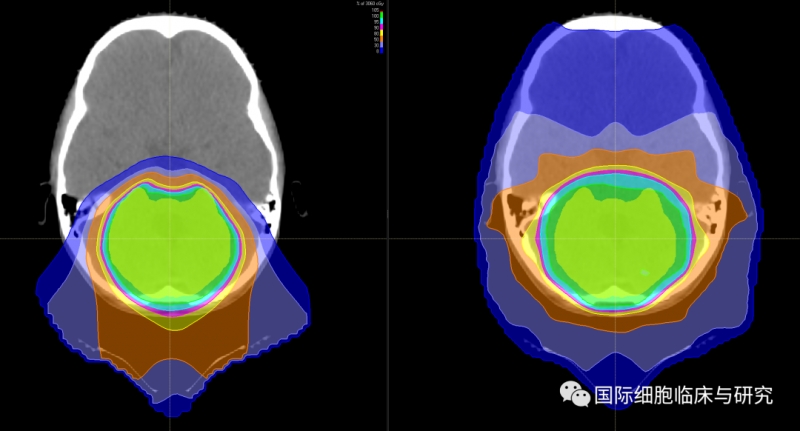

图中左侧为质子疗法的放射剂量分布图像,右侧为光子疗法的放射剂量分布图像;绿色所示区域为目标病灶区域,从红色至蓝色示放射剂量逐渐降低。

我们可以清晰地看到,光子疗法(右)的射线在穿过病灶区域之后仍保持一定的剂量,持续照射至患儿的眼部等部位;而质子疗法(左)的射线在击中病灶区域后照射剂量迅速降低,对于正常组织造成的放射伤害更小。